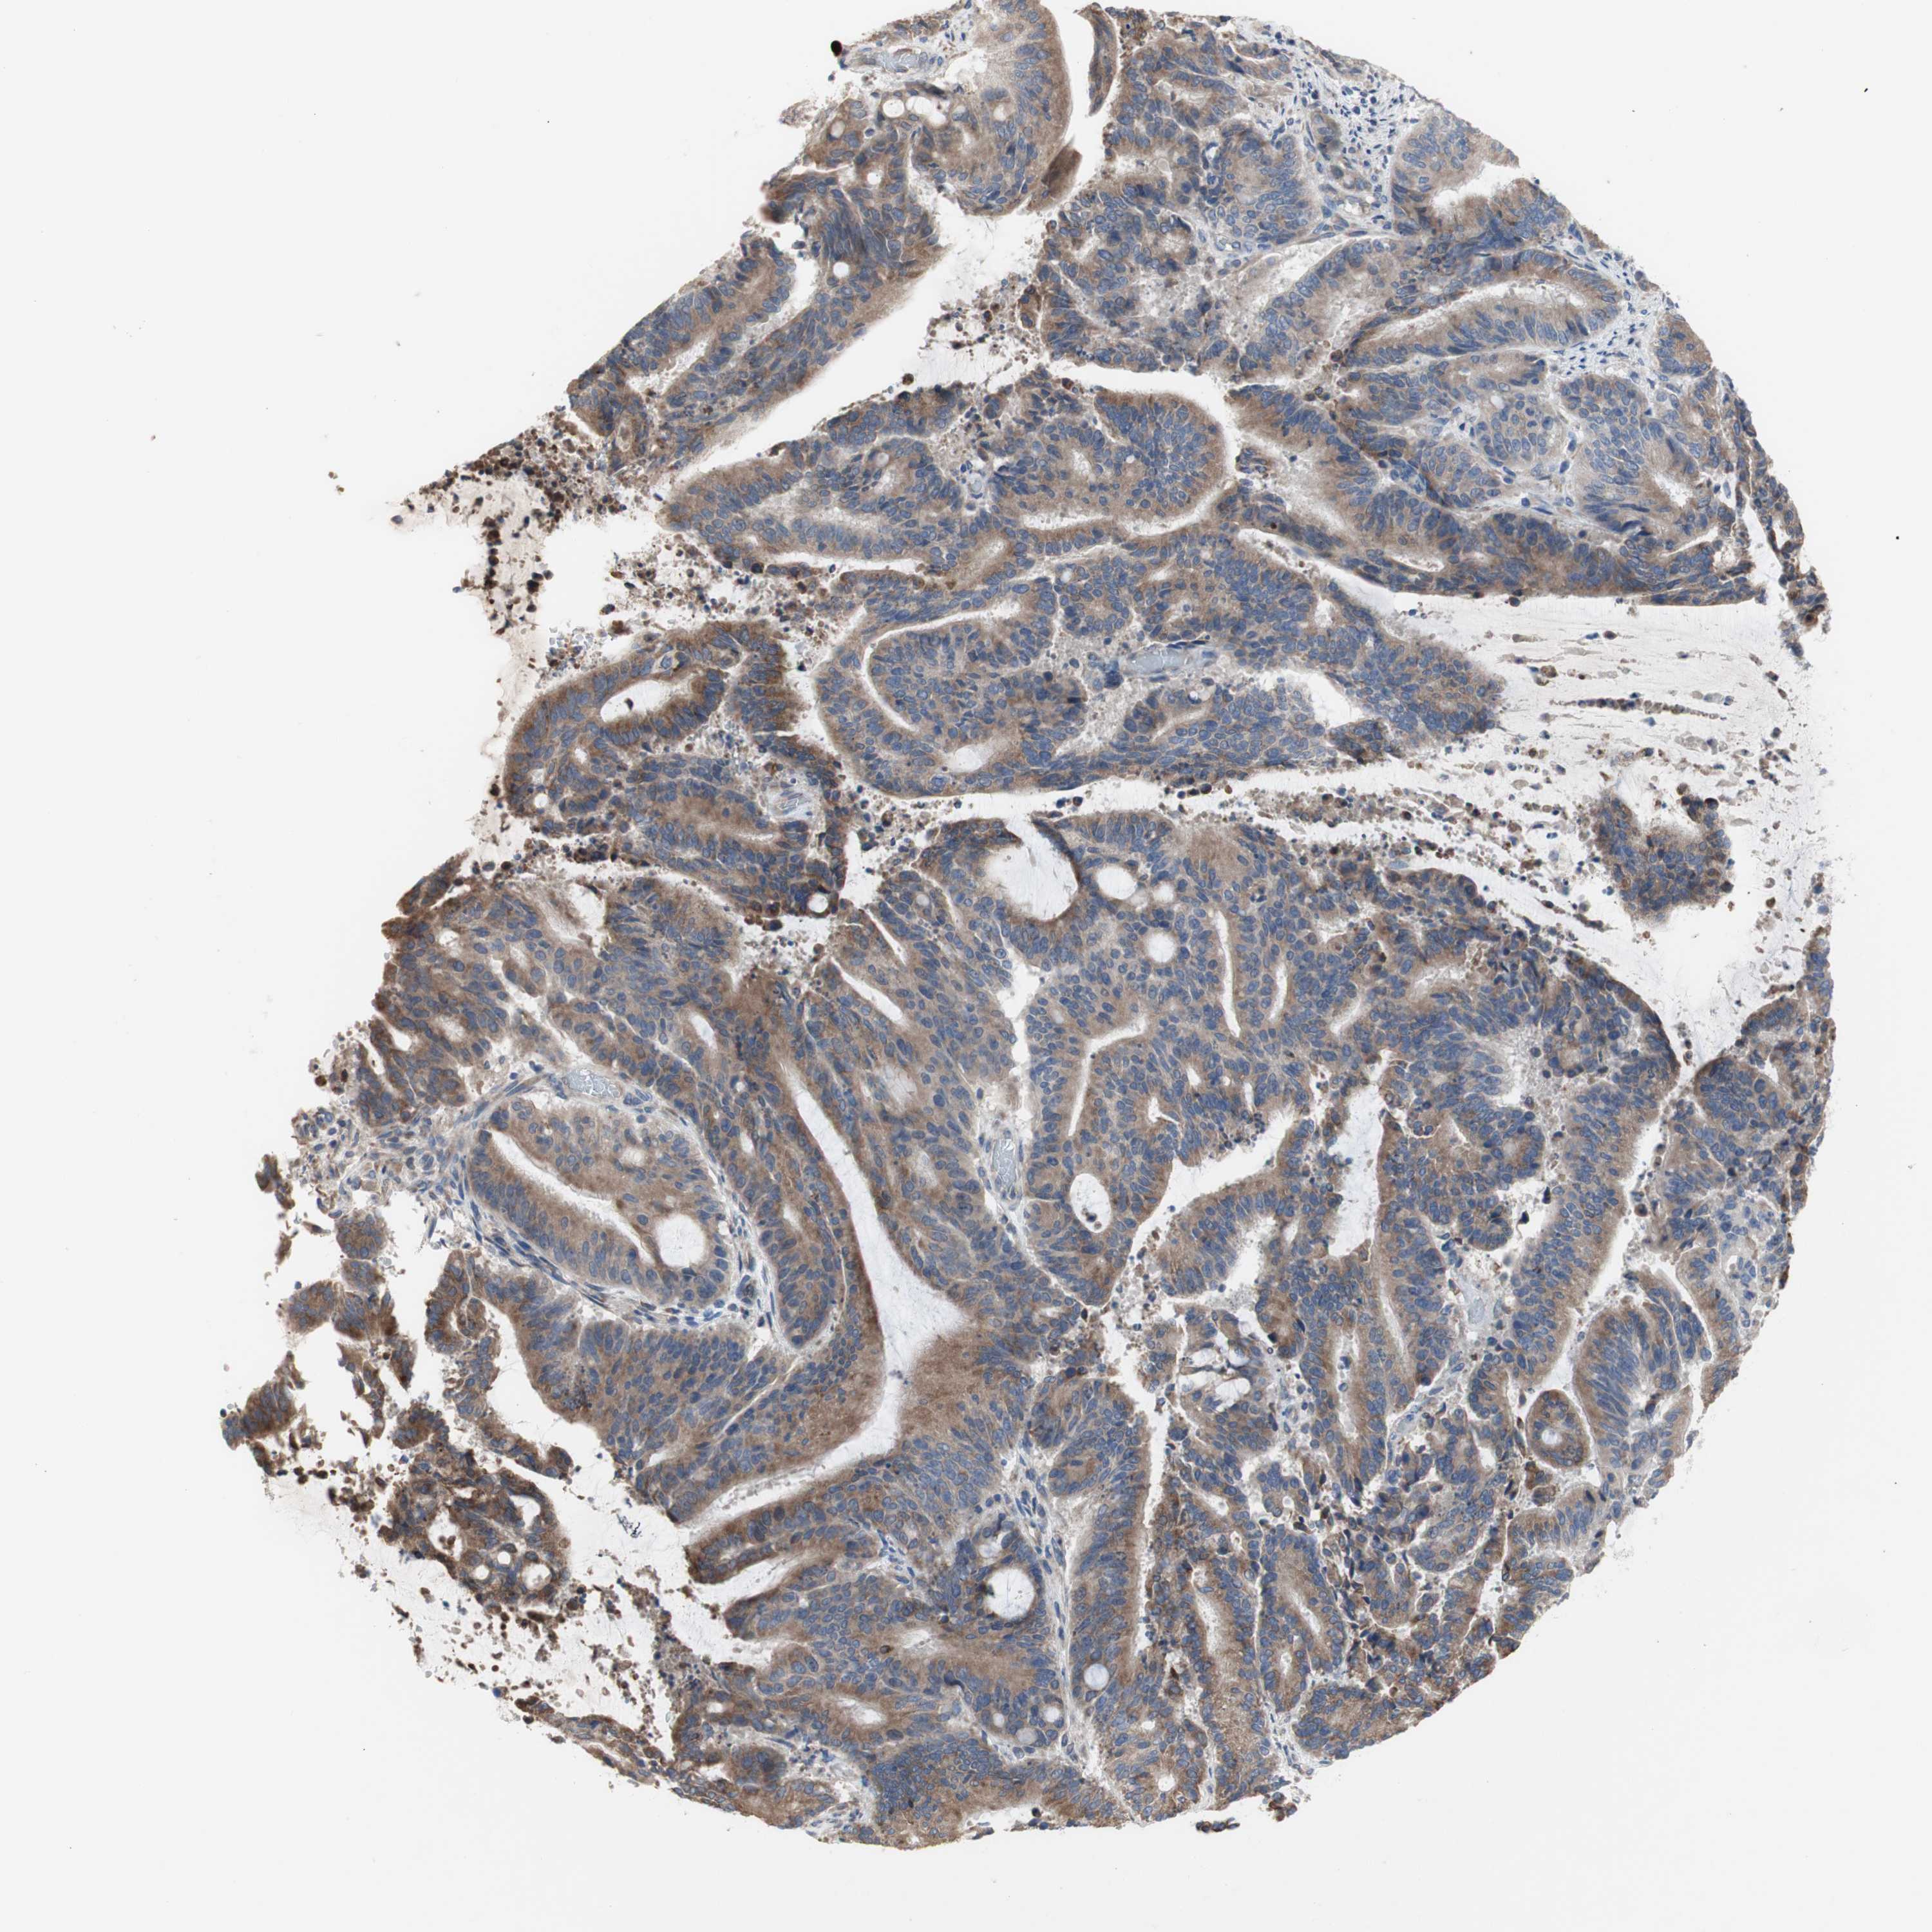

LIVER CANCER - Protein expressioni

A mouse-over function shows sample information and annotation data. Click on an image to view it in a full screen mode. Samples can be filtered based on level of antibody staining by selecting one or several of the following categories: high, medium, low and not detected. The assay and annotation is described here.

Note that samples used for immunohistochemistry by the Human Protein Atlas do not correspond to samples in the TCGA dataset.

Antibody stainingi

Antibody staining in the annotated cell types in the current human tissue is reported as not detected, low, medium, or high, based on conventional immunohistochemistry profiling in selected tissues. This score is based on the combination of the staining intensity and fraction of stained cells.

Each image is clickable and will lead to virtual microscopy that enables deeper exploration of all samples and also displays staining intensity scores, fraction scores and subcellular localization as well as patient and tissue information for each sample.

Antibody HPA009295

Staining

High

Medium

Low

Not detected

Intensity

Strong

Moderate

Weak

Negative

Quantity

>75%

75%-25%

<25%

None

Location

Nuclear

Cytoplasmic/membranous

Cytoplasmic/membranous,nuclear

Cholangiocarcinoma

Carcinoma, Hepatocellular, NOS